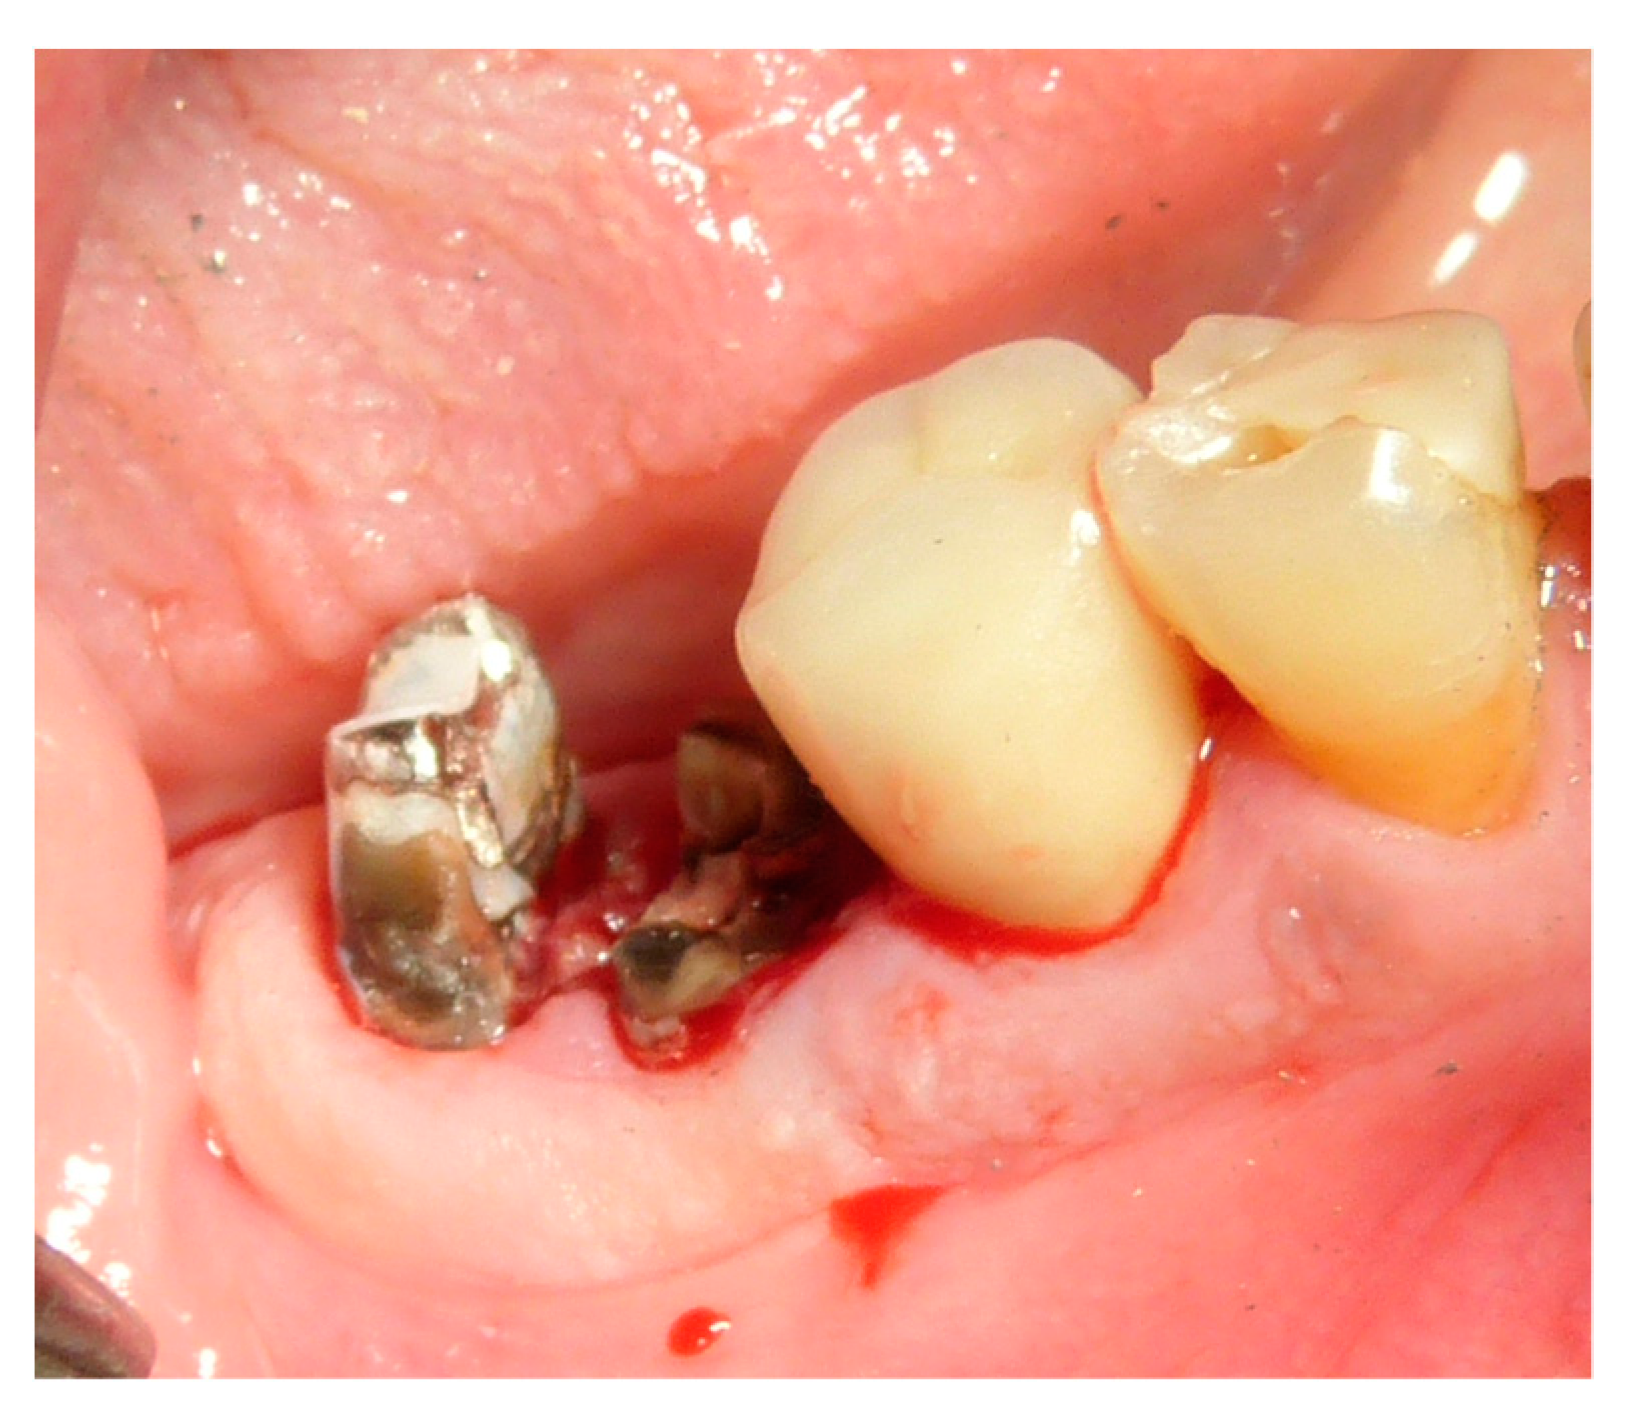

2.5. Surgical Procedures and Follow-Up

| Extraction reasons | Crown trauma |

| external root resorption | |

| Periodontitis | |

| Missing tooth | |

| Root fracture | |

| Infected root | |